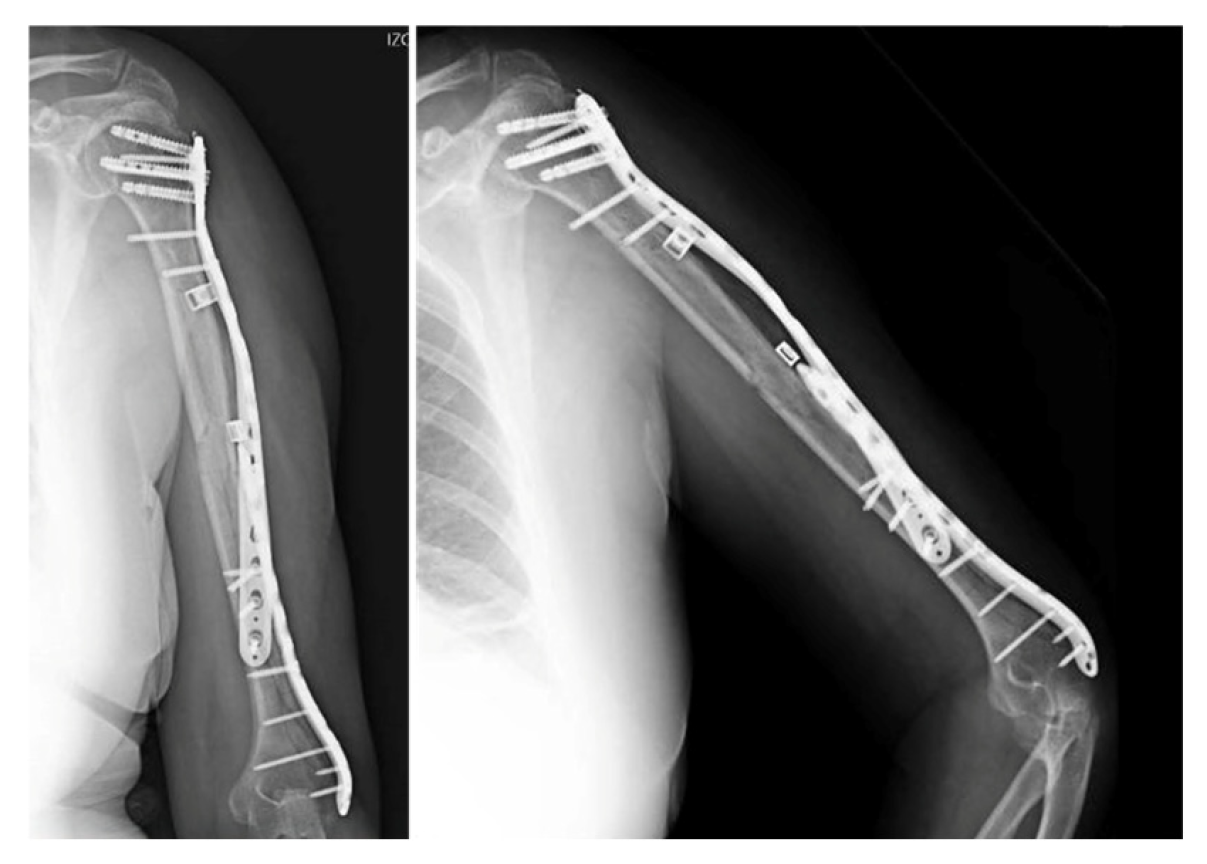

This is the case of a 62-year-old female who was admitted to our hospital following an accidental fall down the stairs that resulted in trauma to her (non-dominant) left upper limb. The patient had a history of ischemic heart disease, and her physical examination revealing pain, deformity and functional disability in the arm. A distal neurovascular examination detected no abnormalities. The radiological examination revealed an AO 12B2 segmental spiral fracture in the proximal third of the humeral shaft [4] (Figure 1).

Figure 1. X-ray of the initial injury, showing a proximal humerus fracture extending into the diaphysis.